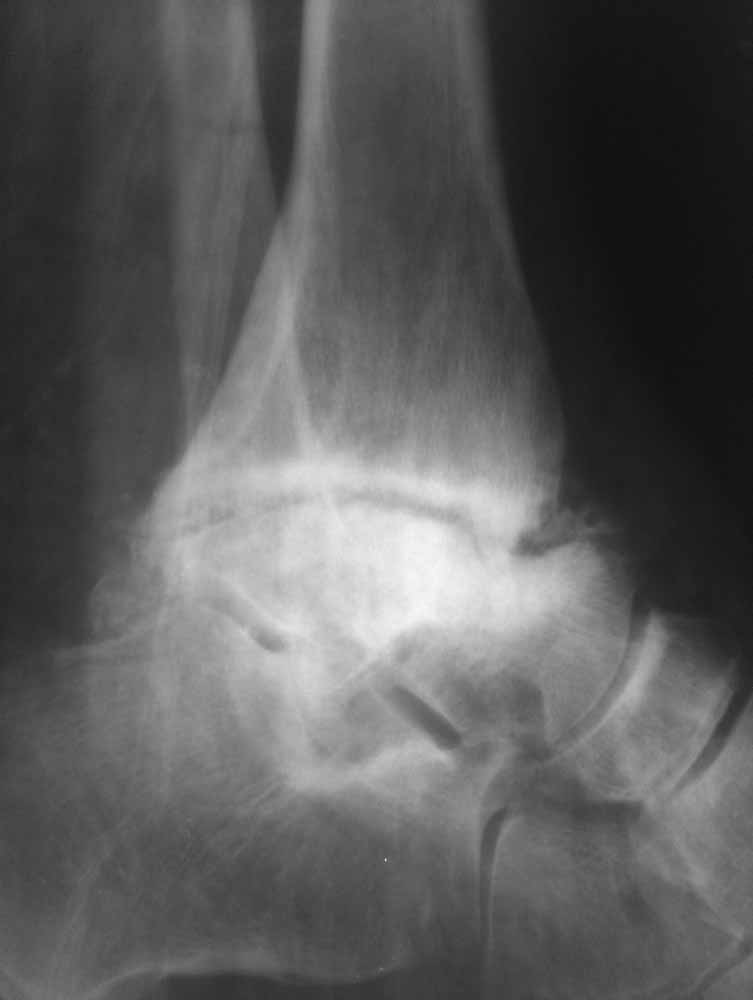

Зачем вытяжение - эффект на рентгенограммах виден.

Склоняемся к мысли, что все таки Charcot's Joint.

Имя     : На вытяжении 1.jpg

Тип     : image/jpg

Размер  : 17247 байтов

Описание: отсутствует

Url     : http://weborto.net:8080/pipermail/ortho/attachments/20111203/f37772b8/attachment-0004.jpg